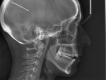

Results:: Ninety-one practitioners and 347 patients were recruited. Demographic characteristics of recruited orthodontists were similar to those of American Association of Orthodontists members. The great majority of practitioners reported using fixed appliances and elastics frequently for adult AOB patients. Only a third of practitioners reported using aligners frequently for adult AOB patients, and 10% to 13% frequently recommended temporary anchorage devices (TADs) or orthognathic surgery. Seventy-four percent of the patients were female, and the mean age was 31.4 years. The mean pretreatment overbite was -2.4 mm, and the mean mandibular plane angle was 38.8°. Almost 40% of patients had undergone orthodontic treatment previously.